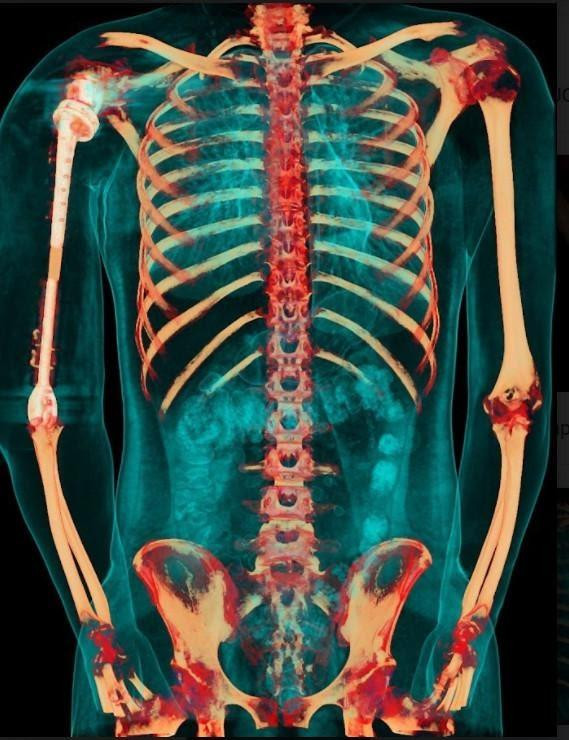

| Ảnh chụp X-quang so sánh xương cánh tay 2 bên sau khi phẫu thuật |

Đặc biệt, công nghệ in 3D được coi là công nghệ duy nhất hiện nay mang lại khả năng cá thể hóa các chi tiết cấy ghép.

Nhờ công nghệ này, cả 3 phần của xương cánh tay nhân tạo đều được “thiết kế riêng” theo đúng kích thước cánh tay thật của bệnh nhân, đồng thời có các điểm cố định giúp khôi phục lại hệ thống gân cơ bám xương.

Trước khi sản xuất, tất cả những thiết kế này đều được thử nghiệm mô phỏng khả năng vận động, chịu lực trên máy tính.

Nhờ vậy, xương nhân tạo sau ghép sẽ tương thích tối đa, “hoàn toàn vừa vặn” với cơ thể người bệnh và thời gian phục hồi chức năng vận động của cánh tay sẽ được rút ngắn đáng kể.